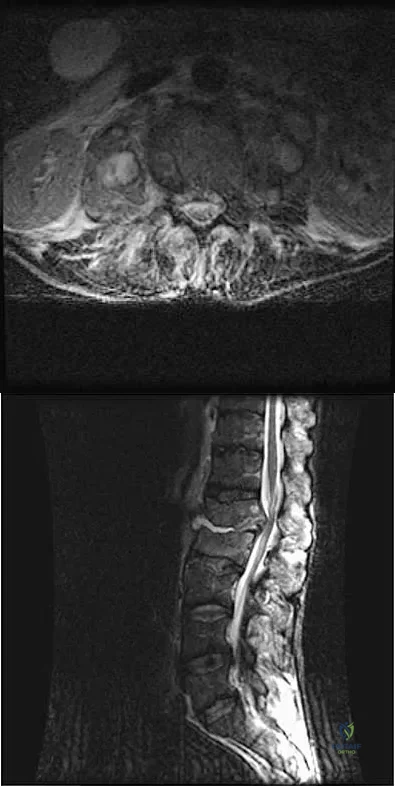

Question 335High Yield

A 32-year-old man notes increasing back pain and progressive paraparesis over the past few weeks. He is febrile, and laboratory studies show a WBC of 12,500/mm3. MRI scans are shown in Figures 6a and 6b. Management should consist of

Explanation

Indications for surgery in spinal infections include progressive destruction despite antibiotic treatment, an abscess requiring drainage, neurologic deficit, need for diagnosis, and/or instability. This patient has a progressive neurologic deficit. Debridement performed at the site of the abscess should effect canal decompression. Once the debridement is complete back to viable bone, the defect can be reconstructed with a strut graft. Additional posterior stabilization is used as deemed necessary by the degree of anterior destruction. CT-guided needle aspiration, while occasionally useful in the earliest phases of an infection, produces frequent false-negative results and would provide little useful information in the management of this patient. Emery SE, Chan DP, Woodward HR: Treatment of hematogenous pyogenic vertebral osteomyelitis with anterior debridement and primary bone grafting. Spine 1989;14:284-291. Lifeso RM: Pyogenic spinal sepsis in adults. Spine 1990;15:1265-1271.

References:

- Beaty JH (ed): Orthopaedic Knowledge Update 6. Rosemont, IL, American Academy of Orthopaedic Surgeons, 1999, pp 713-721.